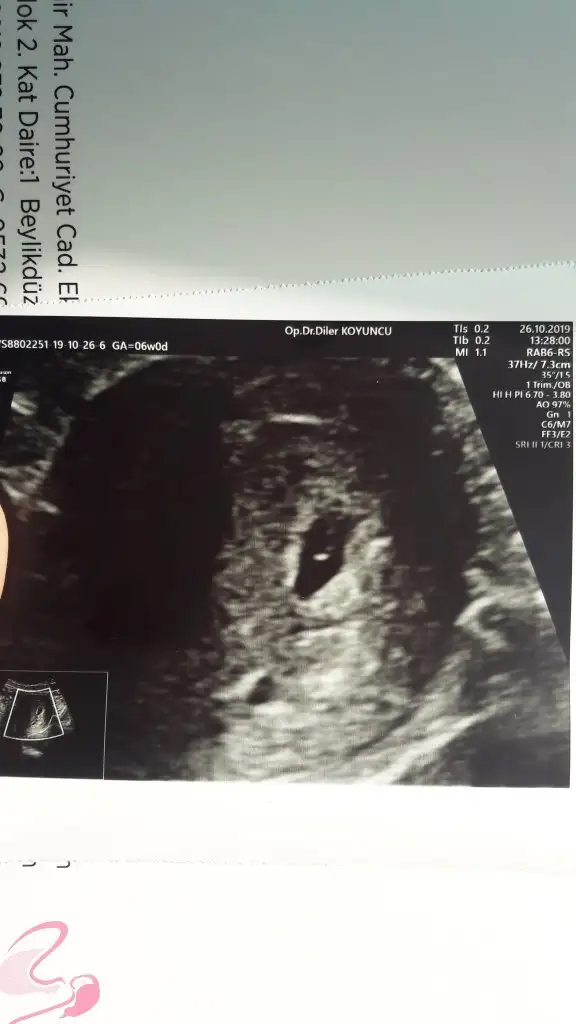

Benim de kesem yuvarlak degil oval seklinde ama ben bebegi goremedim henuz kucukTamam canm aslnda benmkide ikisinin oranı falan çok güzel dedi içm rahat ama ne bilm çoğusnda kese tam yuvarlk bende değil

Ay inşallah görürsn canm..zaten daha bişey açıp okumuyorm doktor iyi dediyse iyidirrrBenim de kesem yuvarlak degil oval seklinde ama ben bebegi goremedim henuz kucuk

Cok sevindim canim hadi gozun aydin darisi banaKızlarrr..bizdde doktordan çıktık şimddi...şükür bebegi gördük kalbndeki hareketide gösterdi ama şuan çok mink duyamayz dedi 9 kasımda diğer randevumuzinşllah o gün duyucaz..kesen güzel büyümüş yolk sac ile oranı güzel bebekte içerde bisorn yok dedi sadece kiloma biraz söylendi.. 1.5 kilo almışım (

Varmı resmi canım ultrason un benimde 10 cm kese demişti sn ne kadar dediBenim de kesem yuvarlak degil oval seklinde ama ben bebegi goremedim henuz kucuk